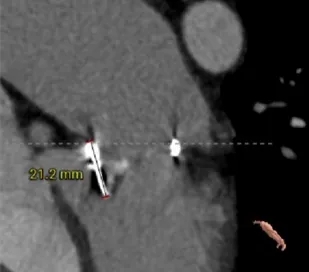

瓣架高度:21.2mm

选瓣依据:该二尖瓣原置换生物瓣型号未知,CT测量生物瓣瓣环周长折算直径约27.6mm,瓣架高度约21.2mm。